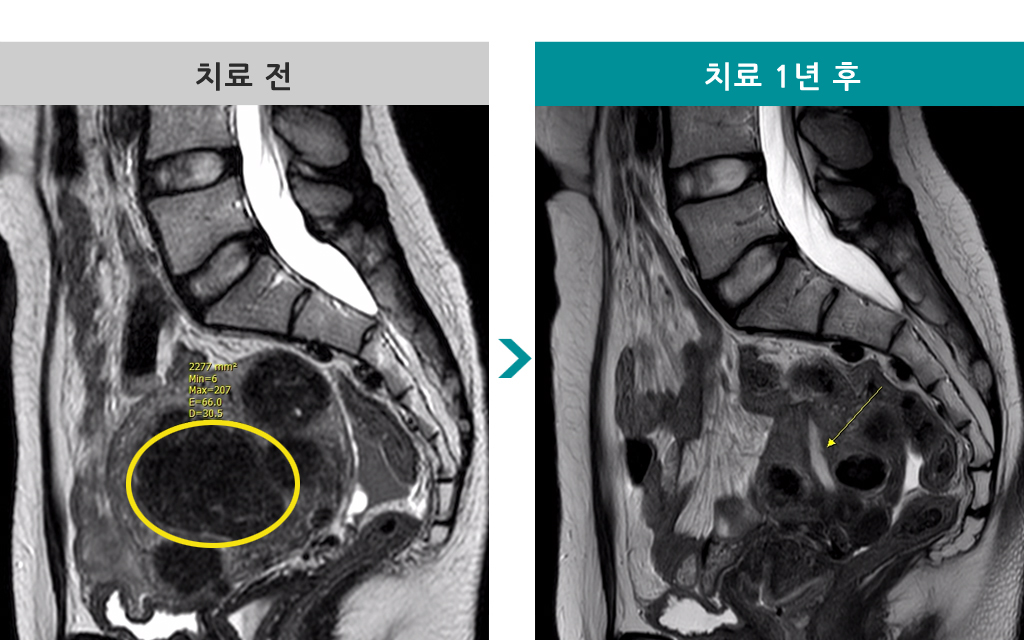

48세 [자궁근종 색전술] 전후 MRI사진 비교